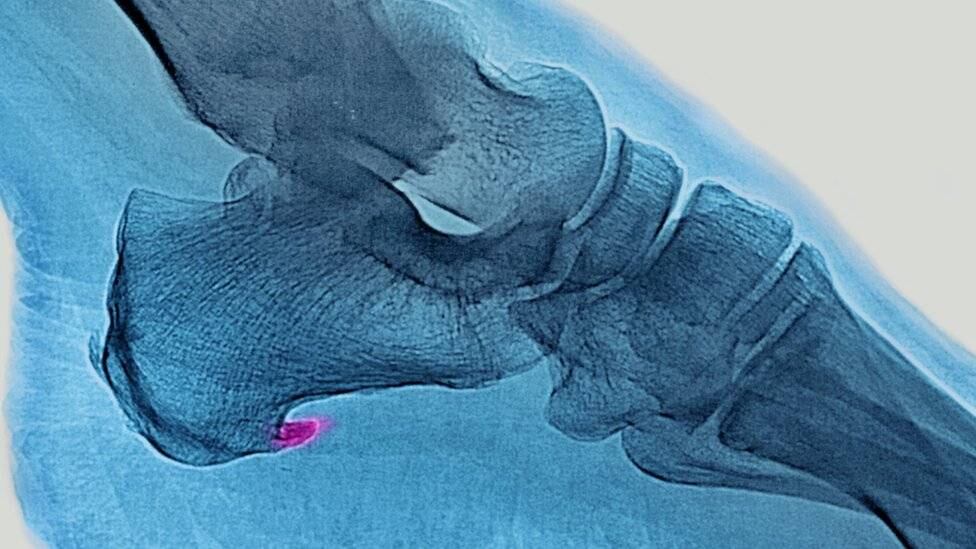

Se trata de un dolor agudo en la planta del pie, justo por delante del talón, que se intensifica cuando nos levantamos o pasamos un período de tiempo sin movernos.

Puede incluso impedir que se levanten los dedos del piso, condicionando la movilidad de las personas.

Hablamos de la fascitis plantar, una de las lesiones más comunes que se puede sufrir a la hora de correr pero que suele pasar desapercibida cuando se está llevando a cabo el ejercicio.

Lo que ocurre es que se produce una inflamación de la membrana que recubre la musculatura de la planta del pie y el talón.